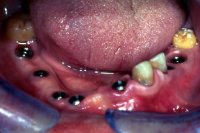

Im Unterkiefer habe ich einige parodontal schwer geschädigte Zähne gezogen und zwei Monate später sieben Implantate gesetzt, wobei bei einigen kleinere Augmentationen gemacht wurden (advanced implantology). Nach sechswöchiger Einheilung der Implantate (Abb. 5 und 6) wurden die Aufbauten in die Implantate eingeschraubt und die verschiedenen Brücken festsitzend zementiert.

Abb. 7 zeigt das Resultat im Unterkiefer nach der Sanierung. Im Oberkiefer läuft dieser Fall unter komplexer Implantologie als Fall 8 weiter.